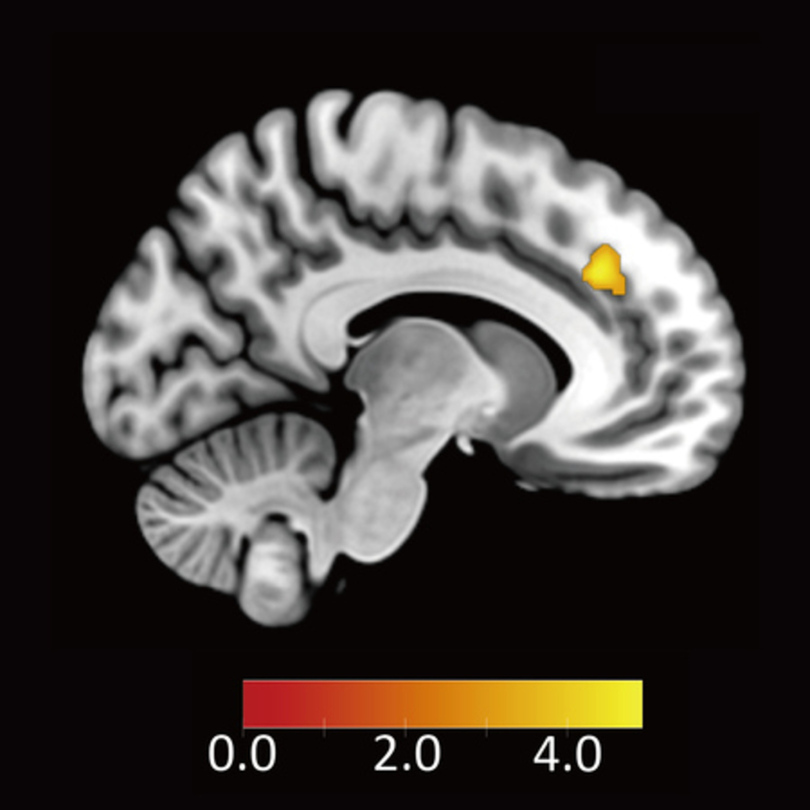

そこで、分配の受入れ/拒否という行動選択と反応時間の両方から意思決定を分析できる「ドリフト拡散モデル(Drift Diffusion Model:DDM)」を用いて解析を行いました。具体的には、「不公平な提案に対する不快な感情を抑えることで提案を受け入れる」という過程に関わる脳部位を明らかにするため、DDM解析を用いて、不公平な提案をより受け入れる参加者ほど、不公平に対して強く反応する脳領域を探索しました。その結果、背側前帯状皮質が見つかりました(図3A参照)。

【画像:https://kyodonewsprwire.jp/img/202601283183-O8-aBK70pTY】

図3(A)不公平な提案を受け入れる参加者ほど不公平に対して反応する脳領域(背側前帯状皮質)